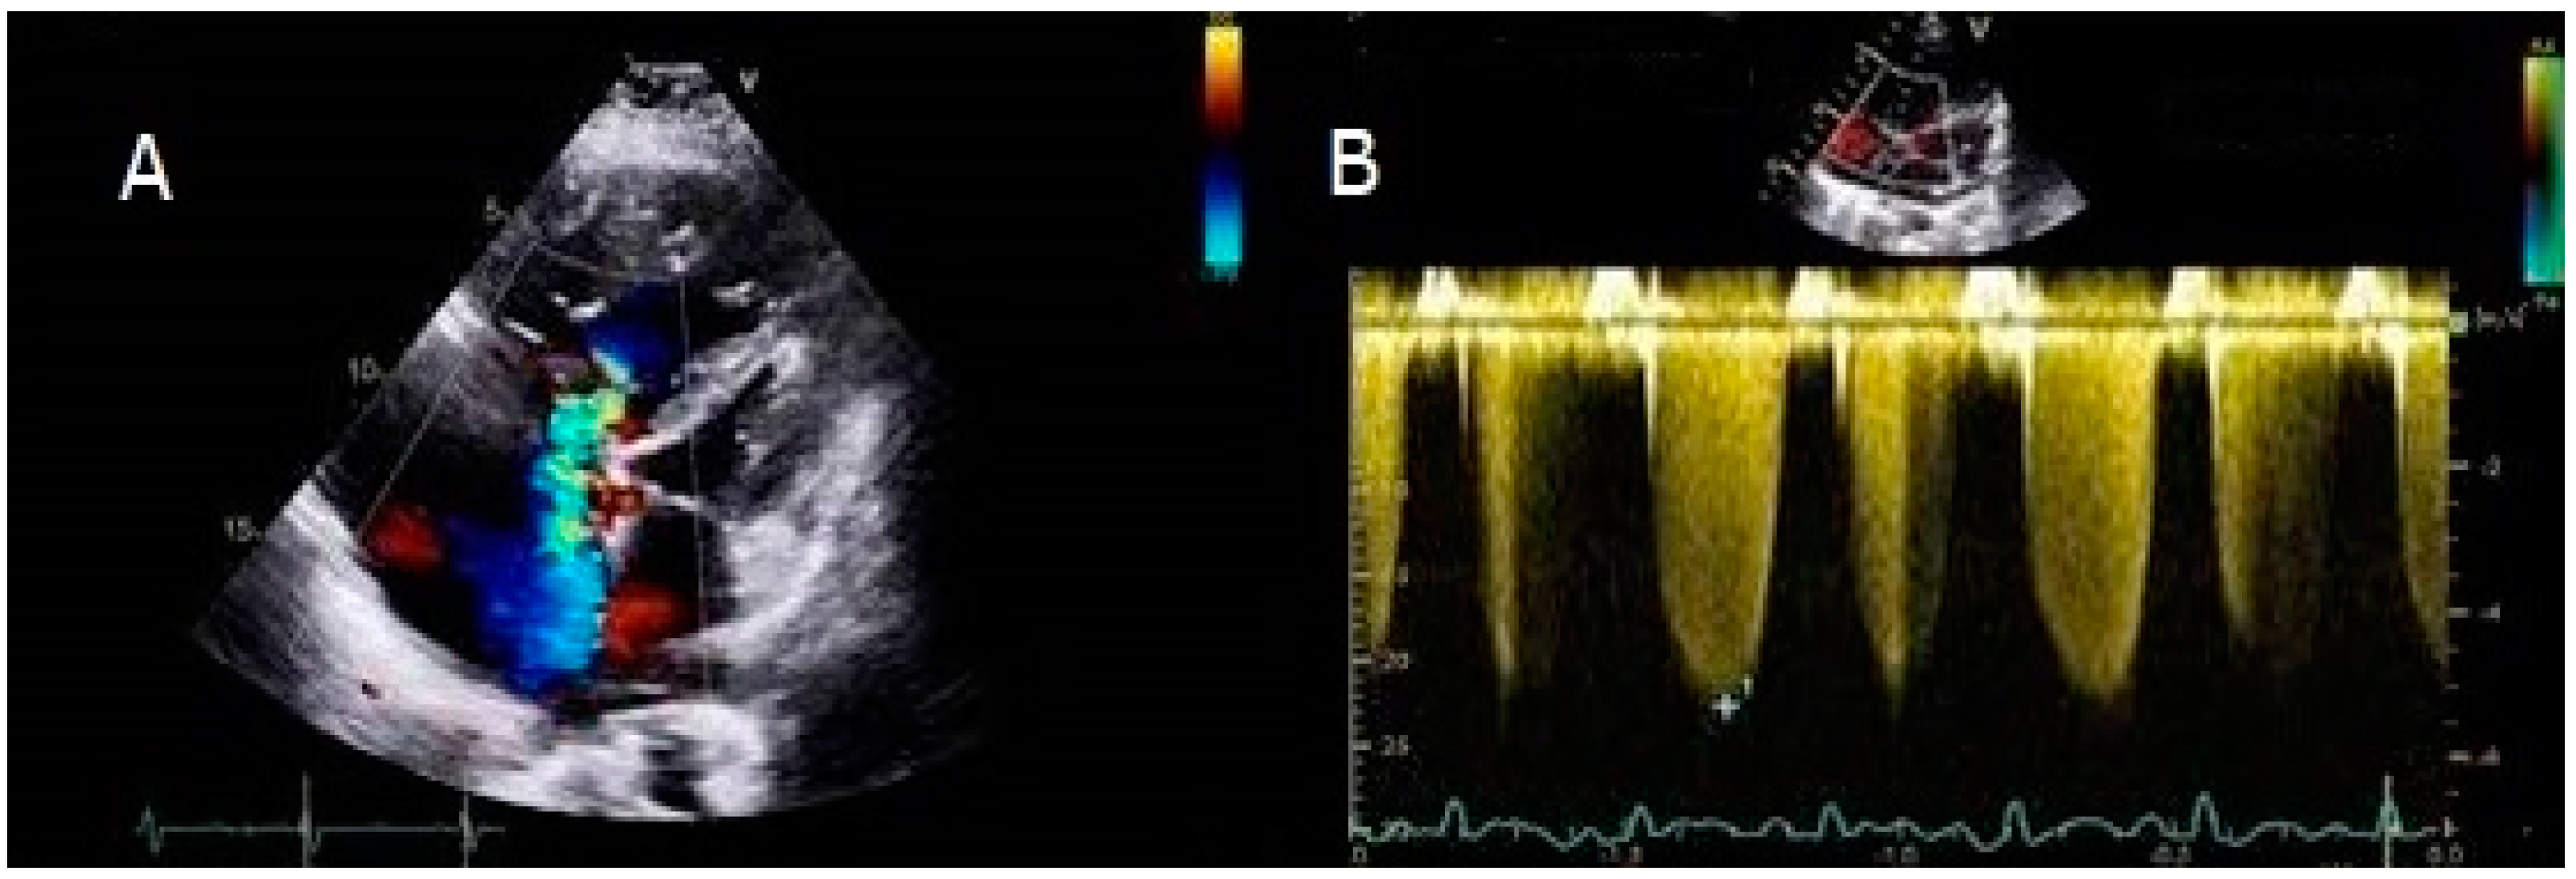

4.1. Case 1

4.2. Case 2

4.3. Case 3